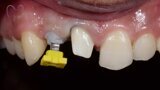

Esthetic Rehabilitation of Maxillary Anterior Teeth: Dr Sanjay Sah